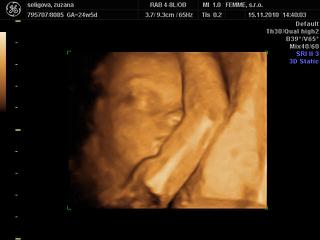

@bebulik aj moj chlap tvrdil, ze plodi len baby a vidis, ake gulky sa nam na uzv ukazali 😀